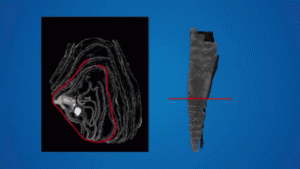

Bilim insanları “tarama” yöntemi ile mumyalara zarar vermeden onları inceleyebiliyor. Ancak aynı durum papirüsler için geçerli değil. Papirüs kağıdına yazılmış olan içerikler onu saran özel kılıfı yok etmeden okunamıyor. Bu da araştırmacıları büyük bir ikilemin içine sokuyor. Mısır’ın günlük hayatına ilişkin verileri içeren bu değerli bilgiyi elde etmek mi, yoksa onu olduğu gibi korumak ama bilgiden mahrum kalmak mı? Bazı bilim insanları bu parçalama yöntemini “acımasızca” bulurken bazıları ise bilginin çok daha değerli olduğu görüşünde. Geliştirilen yeni yöntemle bu ikilemin önüne geçmek mümkün.

Söz konusu yeni yöntem University College London araştırmacıları tarafından geliştirilmiş. Papirüsü koruyan kılıfa farklı frekanslarda ışık göndererek tarama işlemini gerçekleştiren ekip yazıların “parlamasını” sağlıyor. Böylelikle kılıfı parçalamadan neler yazdığını görmek mümkün oluyor. BBC‘nin haberine göre her ne kadar genellikle alışveriş listesi ya da vergilerle ilişkili olsa da söz konusu içerikler Mısır’ın günlük hayatına ışık tutuyor. Bulunan bu teknik başarılı bir şekilde test edildi. Ancak şimdilik genel bir kabul görüp görmeyeceği bilinmiyor. Ancak söz konusu teknikle beraber pek çok kalıntıya zarar vermeden yeni şeyler keşfetmek mümkün. 2.000 yıllık papirüsleri okumakla başlayan bu keşif tarihe ışık tutabilir.